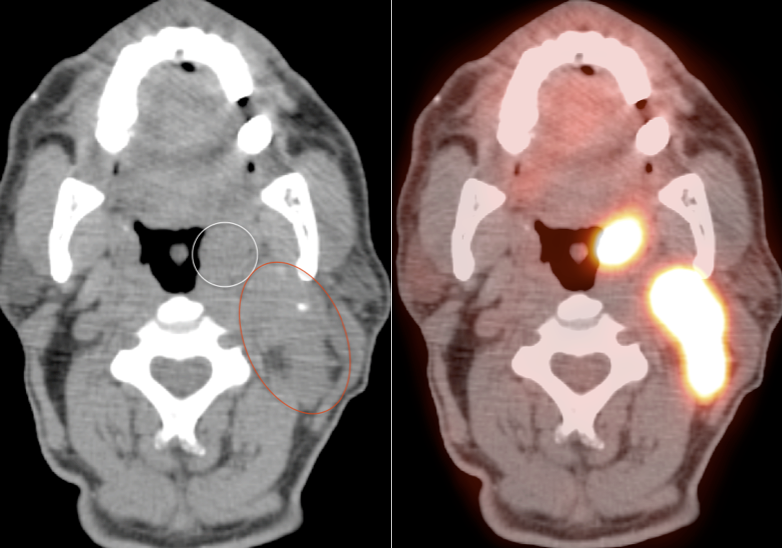

Tonsillar (Palatine) Carcinoma

- The majority of patients with tonsillar carcinoma have a biopsy-proven diagnosis prior to PET/CT scanning. In such cases, any increased FDG uptake involving a tonsil typically represents the cancer (prior to therapy).

- Many patients will present with the diagnosis of metastatic SCCA of unknown primary. A tonsillar primary must be excluded in these patients.

- Lastly, on rare occasion, an incidental tonsillar carcinoma cancer will be identified.

Unilateral FDG-Avid Tonsil (or Relative Increased Avidity of One Tonsil):

Special care is required when assessing the incidental finding of a unilateral hot tonsil (or relative increased uptake within one tonsil) — even though most unilateral hot tonsils are benign. Proposed techniques for assessment have included SUV threshold cutoff values, metabolic tumor volume assessment, and SUV ratios.

Unfortunately, it is advisable to raise at least a degree of concern for most FDG-avid unilateral tonsillar findings. The level of suspicion, of course, depends on the presentation.

- Any Unilateral Tonsillar Uptake Associated with Hypermetabolic Cervical Nodes:

Clearly, the presence of hypermetabolic cervical nodes dramatically increases the likelihood of malignancy (and the confidence of your reporting).